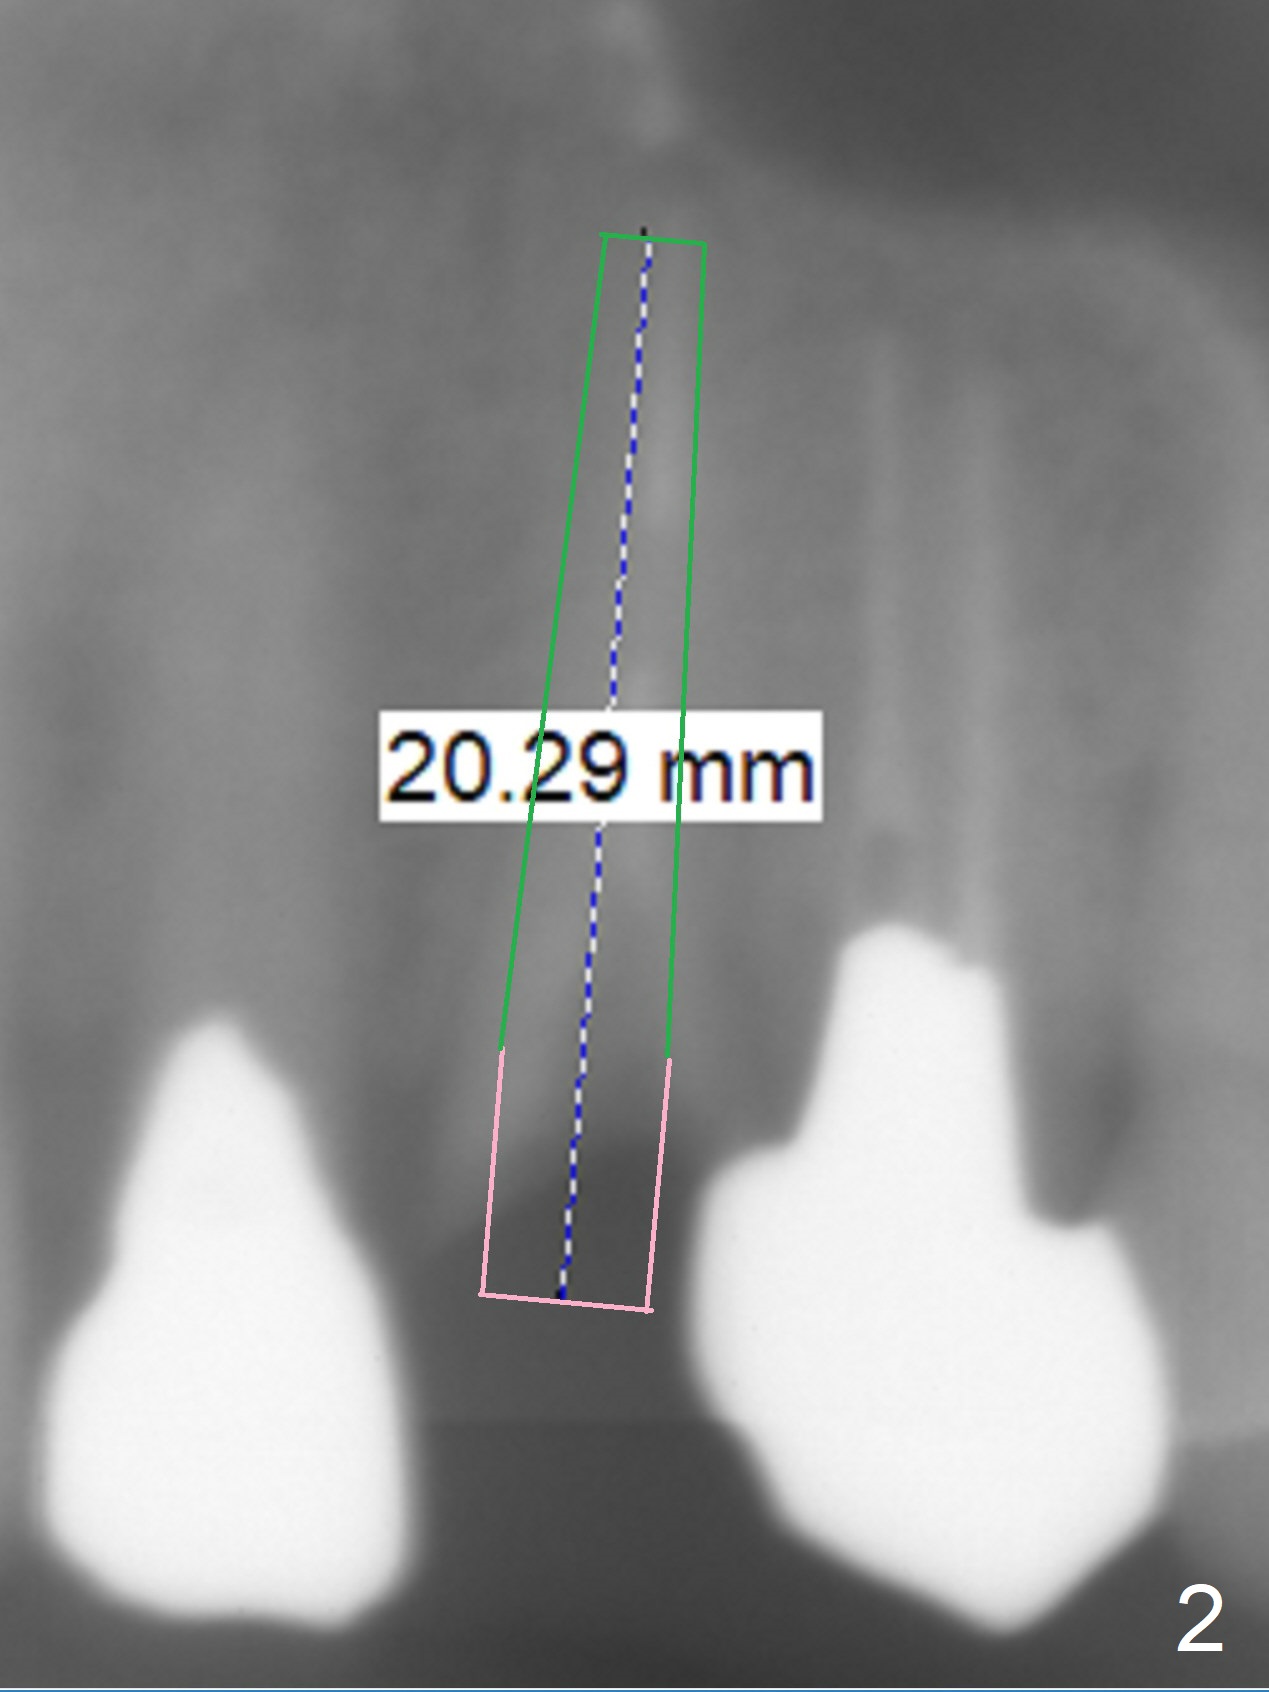

A 50-year-old man has multiple restoration (Fig.1). The tooth #11 has equigingival fracture (Fig.2). Since the labial bone is thin, socket shield will be done.